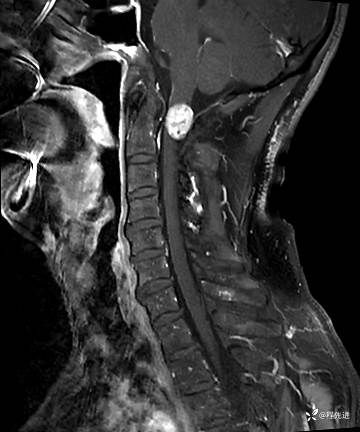

MRI平扫+增强:

T2: